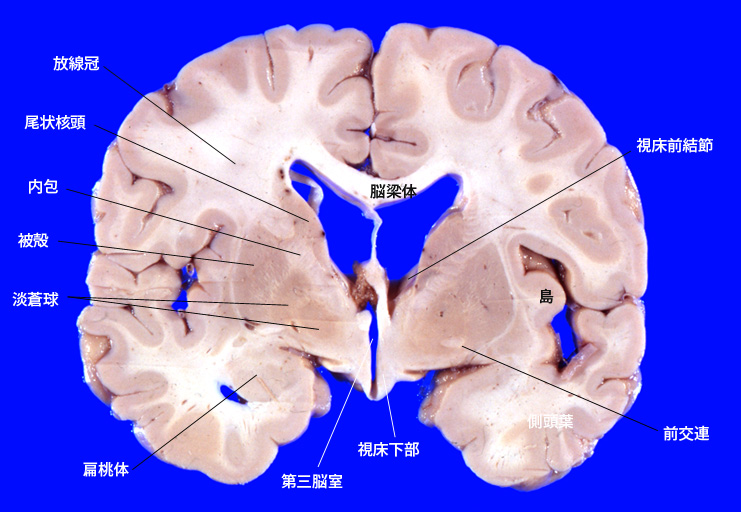

6. 視床下部、前交連をとおる断面

7. 線状体(尾状核+被殻)頭部をとおる前頭断面